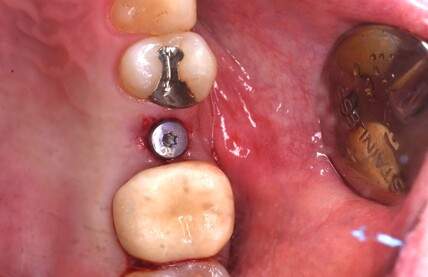

口腔内写真

- Befor

- After

| 年齢 | 50代・男性 |

|---|---|

| 主訴 | 部位:左下6番7番 主訴:左下奥歯腫れて痛い。 |

| 治療内容 | 左下6番抜歯、左下6番7番骨造成、インプラント埋入 |

| 治療費 | 合計:1,232,000円 ・内訳 診断料:55,000円 サージカルガイド2本:66,000円 GBR:110,000円×2本 埋入料:165,000円×2本 静脈内鎮静麻酔:77,000円 2次OPE:22,000円×2本 仮歯:55,000円×2本 上部構造(フルジルコニア):165,000円×2本 (2023年1月現在) |

| 治療期間 | 約8ヶ月 |

| リスク・副作用 | リスク・副作用 |

| 治療方針 | 元々支台歯に負荷がかかりやすいとされている延長ブリッジを抜歯し、1本単体でしっかりかめるようにインプラントを2本埋入した。骨吸収も進んでいたため、※GBR法で骨造成を同時に行った。 治療と並行して、全顎的な歯周病治療も行い、今後は歯周病が進行しないよう、こまめにメンテナンスに通っていただく。 |

| 特記事項 | ※1 GBR・・・骨再生誘導法。骨の高さや厚みを人工骨や人工膜などを使用し再生する方法 |

| 担当者所見 | 6番は歯根分割された被せ物が7番の欠損部との延長ブリッジとされており、強い咬合と歯周病も相まって負荷がかかり動揺し、歯として機能しなくなったため、抜歯となった。 |